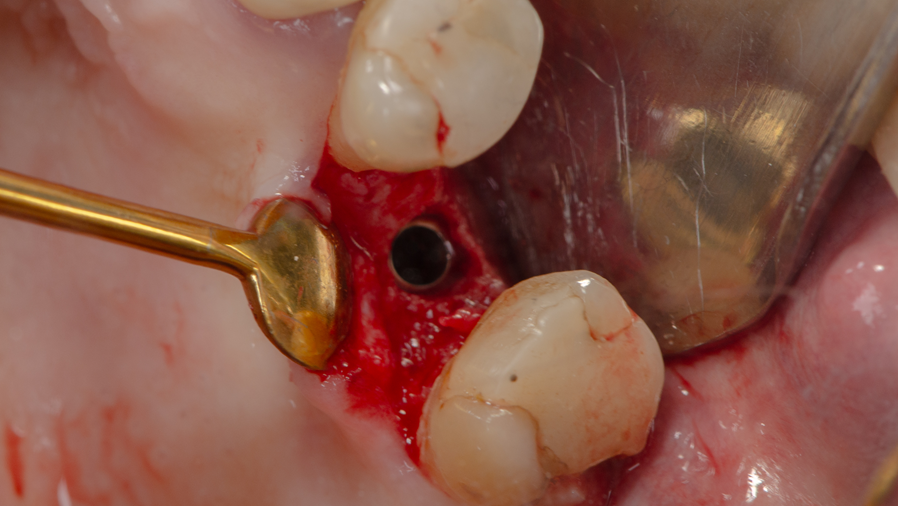

Sob anestesia local, realizou-se incisão crestal na área edêntula do dente 16. O sítio foi marcado com broca lança e fresado conforme protocolo Implacil Osstem para implantes de 4,0 mm. O implante Maestro Superiore 4,0 × 9 mm foi instalado, apresentando torque progressivamente elevado até a posição final, com plataforma 2 mm infraóssea. O torquímetro registrou 50 Ncm, confirmando excelente estabilidade primária, condição favorável para carga precoce ou imediata, em linha com a literatura que destaca a alta fixação inicial dos implantes Maestro sem comprometer o osso circundante.

Acoplou-se imediatamente um cicatrizador ao implante, afim de facilitar o momento de reabertura e foi realizada a sutura.